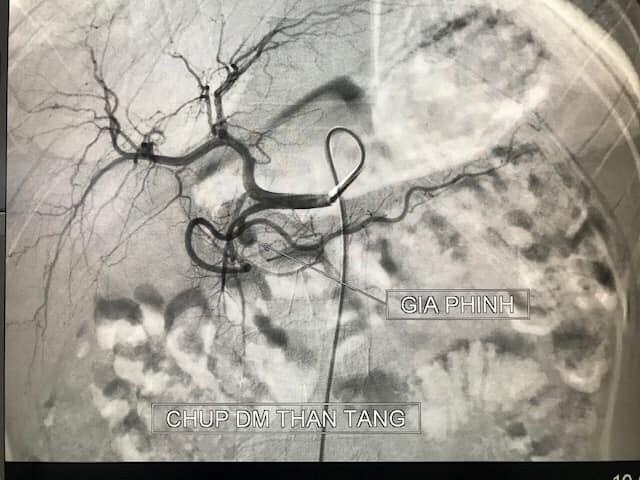

Tình trạng bé tiếp tục diễn tiến xấu, suy hô hấp tăng dần, sốc, rối loạn nhịp tim. Các bác sĩ tiếp tục chống sốc, truyền dịch, truyền thuốc adrenalin, đo huyết áp xâm lấn và áp lực tĩnh mạch trung tâm, điều chỉnh toan chuyển hóa và điện giải.